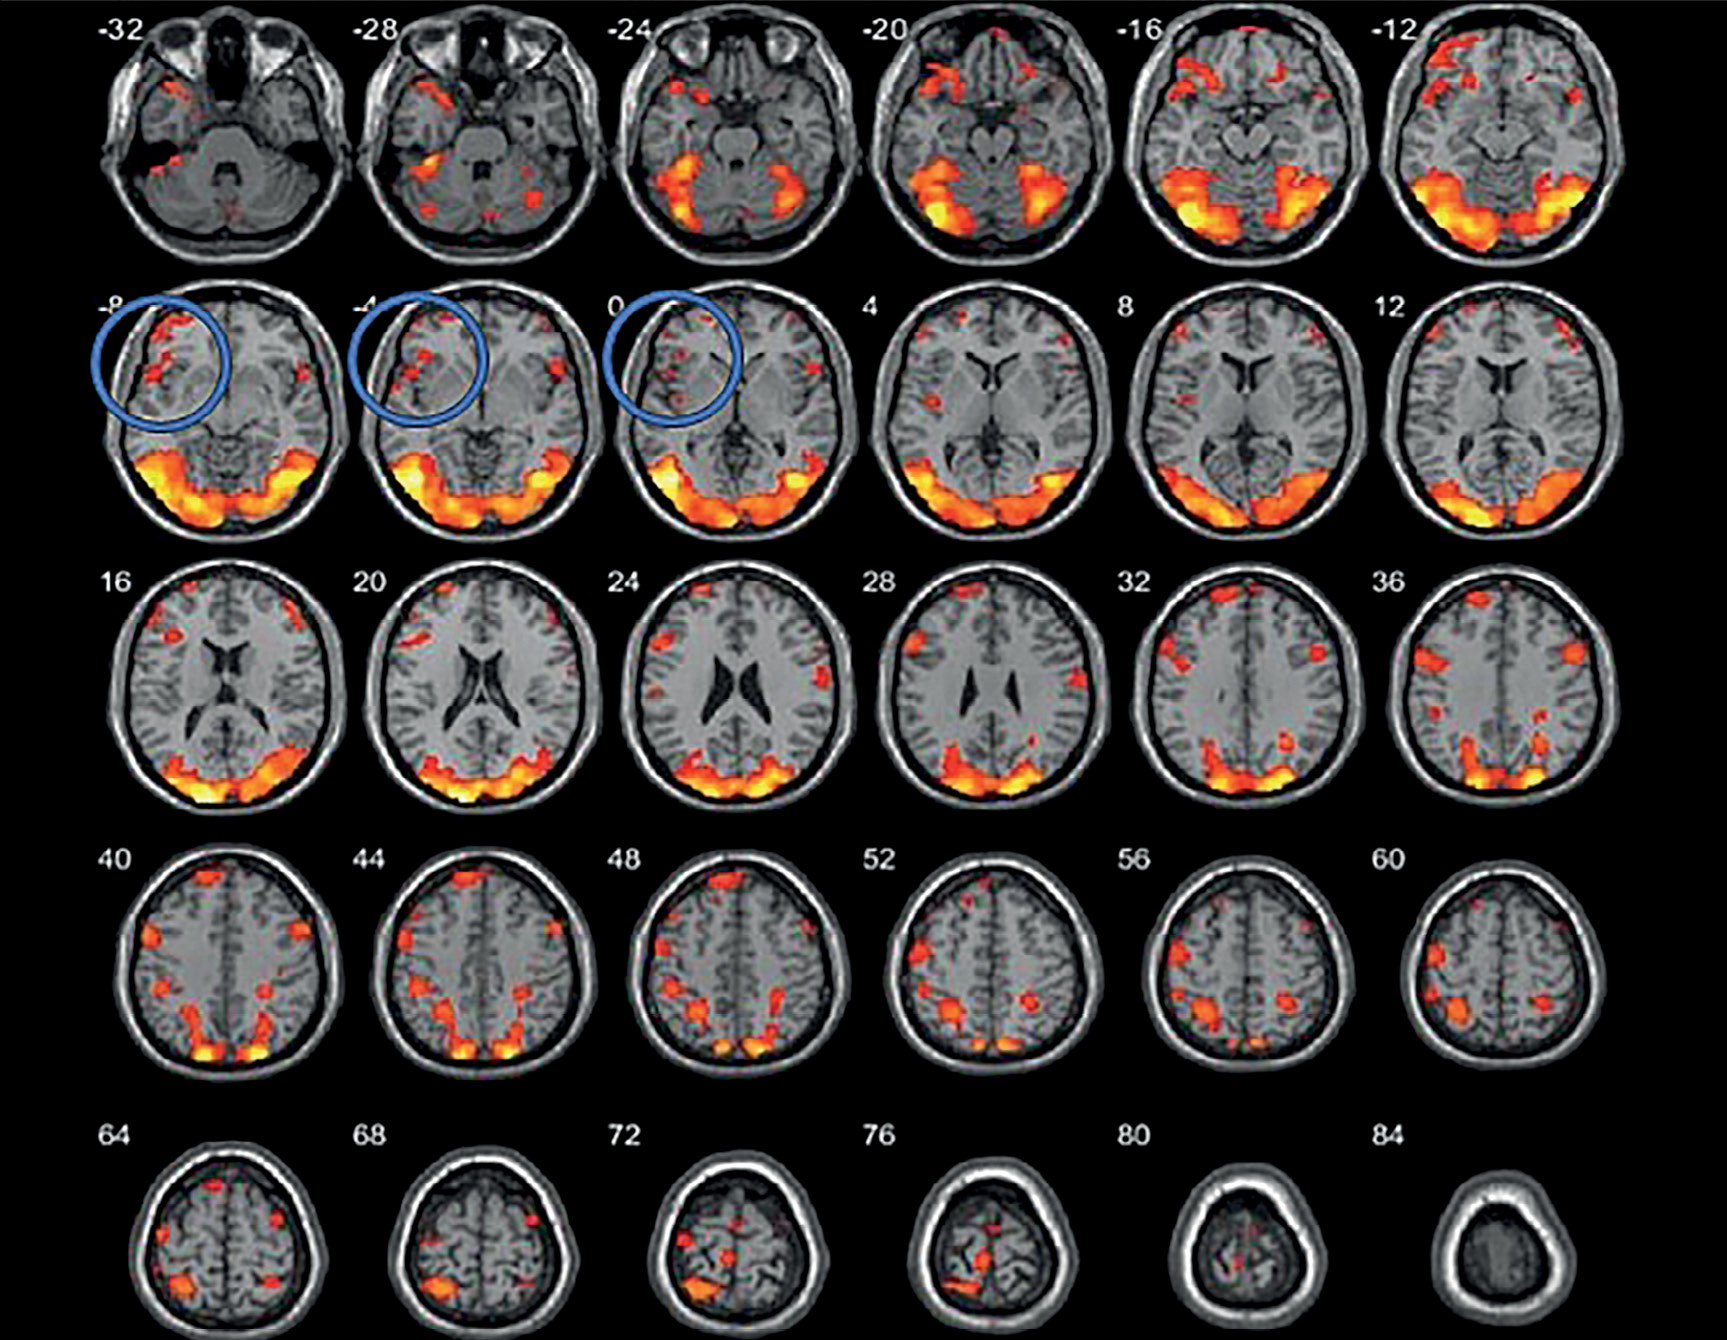

Обеим пациенткам проводилась высокочастотная ритмическая нТМС левой ДЛПФК с использованием следующего протокола: частота стимуляции – 20 Гц, интенсивность стимуляции – 100% моторного порога покоя, длительность пачки стимулов – 2 с, длительность интервала между пачками – 28 с, общее количество стимулов за сессию – 2400. Моторный порог покоя определялся в «горячей точке» как минимальная интенсивности стимуляции, при которой не менее чем 5 стимулов из 10 вызывают формирование вызванного моторного ответа (ВМО) с амплитудой более 50 мкВ при условии полного расслабления исследуемой мышцы. Ритмическая нТМС проводилась на аппарате Magstim Rapid 2 (Великобритания), калиброванном под нейронавигационную систему, с использованием восьмиобразной катушки. Курс лечения обеих пациенток включал 18 сеансов, проводимых с понедельника по субботу включительно с перерывом на 1 день (воскресенье) последовательно в течение 3 нед. Важно отметить, что, в отличие от большинства исследований, в которых мишень для стимуляции выбирается стандартно по анатомическим ориентирам, в данном случае использовался персонализированный подход к подбору мишени на основе анализа данных функциональной МРТ (рис. 1, 2). МРТ-исследование проводилось на томографе Siemens MAGNETOM Verio с индукцией магнитного поля 3 Т. Для получения структурной МРТ использовался режим Т1-градиентное эхо (основные параметры режима – время повторения 1900 мс, время эхо – 2,47 мс, толщина среза – 1 мм, 176 сагиттальных срезов, полностью покрывающих головной мозг). Структурные данные в дальнейшем импортировались в систему навигационной ТМС. Для локализации мишени для стимуляции проводилась функциональная МРТ в режиме Т2-градиентное эхо (время повторения – 3000 мс, время эхо – 30 мс , толщина среза – 3 мм, 36 аксиальных срезов) с применением блоковой зрительной парадигмы собственной разработки, с чередующимся предъявлением нейтральных стимулов (спокойные пейзажи) и высококалорийной пищи (исследование проводилось натощак) (рис. 3, 4).

Рисунок 4. Данные функциональной МРТ (до лечения), синим выделена область активации в зоне интереса (левая ДЛПФК) (пациентка Д.)

По данным фМРТ с пищевой парадигмой, на фоне проведенных сеансов рТМС определяется снижение активации в проекции левой ДЛПФК, которое в рамках настоящего исследования может быть расценено в контексте изменения пищевого поведения. У обследованных такая фМРТ картина сопутствовала снижению аппетита и уменьшению калорийности потребляемой пищи. Исследование было выполнено на следующий день после проведенного курса лечения (рис. 5, 6).

Рисунок 6. Данные функциональной МРТ (после лечения): отмечается отсутствие активации в зоне интереса (левая ДЛПФК) (пациентка Д.)